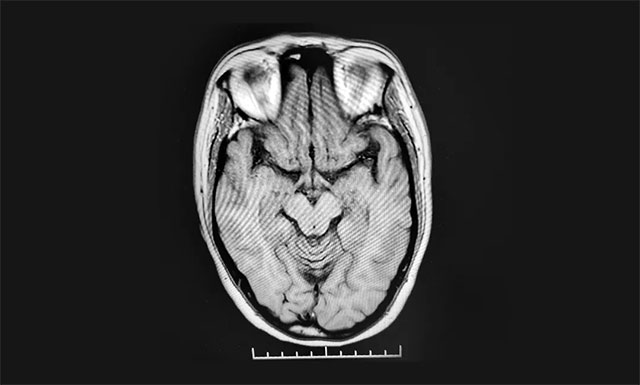

病史資料顯示,黔女士近1個(gè)月來反復(fù)出現(xiàn)頭暈、頭痛,視物旋轉(zhuǎn),右側(cè)顏面部痛覺減低,右側(cè)上肢持續(xù)性麻木、脹痛、抓握不能,右下肢乏力、行走不穩(wěn),左側(cè)肢體感覺異常,并逐漸加重。入院后MR檢查顯示雙側(cè)額葉皮層下微缺血灶。結(jié)合病史和影像資料等,黔女士被診斷為腦梗死(腦干梗死),瓦倫貝格綜合征。

▲ 患者腦干梗死